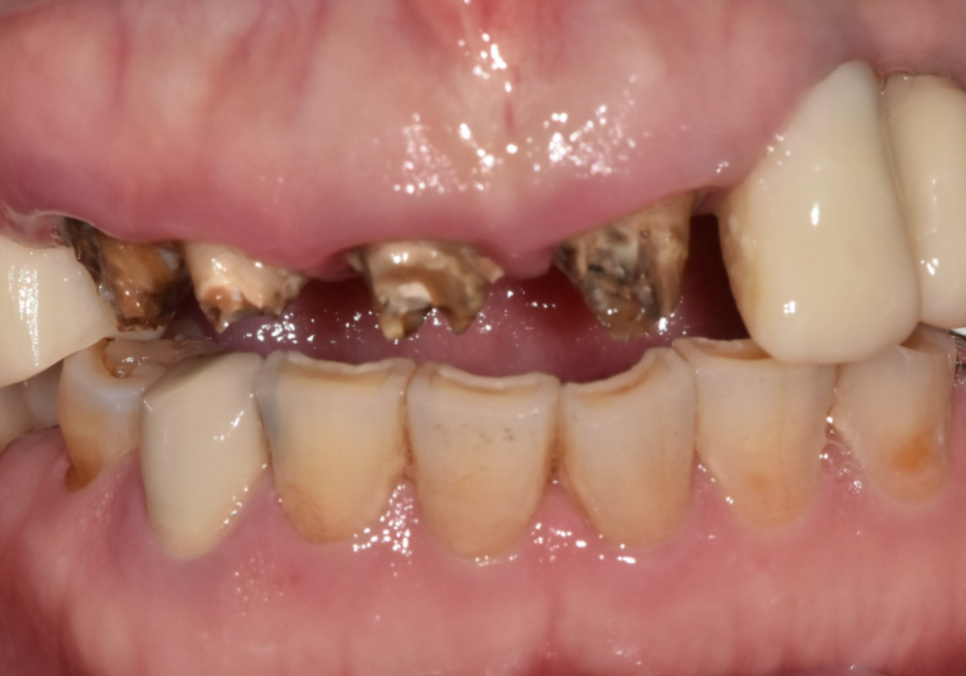

얼마 전 저희 치과를 방문하신

환자분의 이야기예요.

오래전 오른쪽 아래 어금니를

브릿지로 씌우셨는데

해당 부위에서 냄새가 나고

음식물이 너무 많이 껴서 내원하셨다고 해요.

입안을 꼼꼼히 살펴보니 맨 끝 어금니(#47)는

이미 오래전에 뽑으신 상태였고

세 개의 치아(#44~46)를 하나로 묶은

브릿지를 쓰고 계셨습니다.

자세히 살펴보니, 잇몸 쪽으로

치아 뿌리가 살짝 드러나 있고

그 틈으로 음식물이

끼어있는 모습이 관찰되었죠.